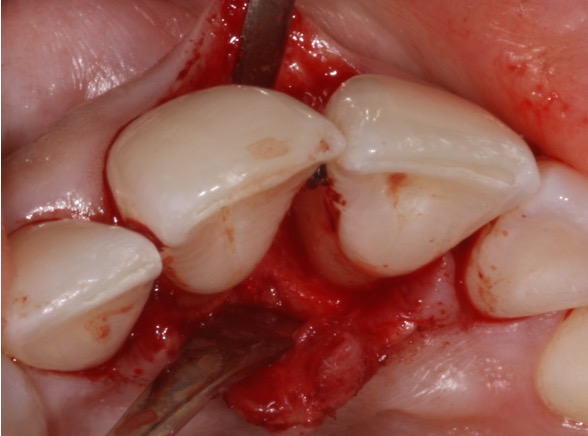

Regenerative periodontal surgery

Periodontal surgery is done in discrete areas of persistent disease that has not responded to non-surgical treatment. In this case a regenerative approach was done to “build-up” the bone. It can only be done in certain scenarios but can significantly improve the tooth’s prognosis